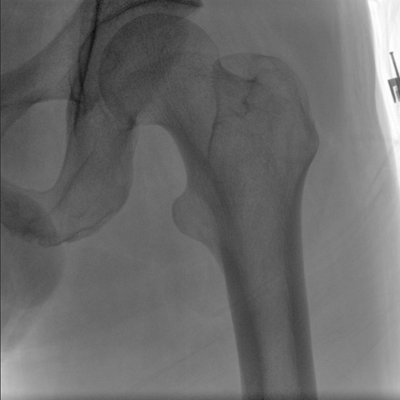

臨床適用科室:骨科、普通外科、矯形外科、創傷外科、泌尿外科、脊柱外科、疼痛外科、消化科、婦科等科室。

大尺寸動態平板探測器,高DQE、低噪聲、圖像清晰。采用多分辨率圖像增強處理技術,不同部位不同圖像處理算法,滿足客戶多樣化的需求。

采用智能變頻脈沖透視技術,優化圖像質量的同時降低輻射劑量,呵護醫患健康